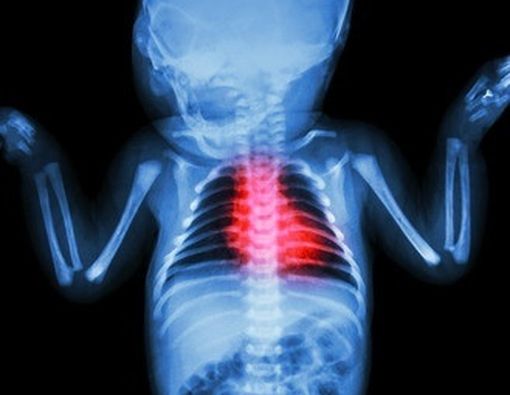

Klikdokter.com - Mungkin Anda pernah mendengar kata-kata bayi lahir dengan ‘jantung bocor’, jantung bayi di kanan, kelainan klep jantung bayi, dan lain sebagainya. Kelainan-kelainan tersebut dalam dunia medis masuk ke dalam kategori peyakit jantung bawaan (PJB) atau sebutan lainnya penyakit jantung kongenital.

PJB adalah kelainan struktur jantung yang muncul sejak lahir dan terjadi sejak janin di dalam kandungan. Kelainan tersebut terjadi akibat jantung atau pembuluh darah disekitarnya tidak berkembang dengan sempurna dan/atau akibat kelainan posisi jantung dan pembuluh darah di sekitarnya. PJB merupakan penyebab umum kelainan bawaan dan penyebab utama kematian bayi akibat kelainan bawaan dalam satu tahun pertama kehidupan. Setidaknya 8 dari 1000 bayi lahir dengan cacat jantung setiap tahunnya. Diperkirakan sekitar 45 ribu bayi lahir di Indonesia dengan PJB setiap tahunnya.

Terdapat berbagai macam jenis PJB. Secara garis besar PJB dibagi menjadi dua kelompok besar yaitu PJB sianotik (biru) dan asianotik (tidak biru). Sianosis mengacu pada perubahan warna kebiruan pada kulit dan selaput lendir terutama pada bibir, lidah, dan ujung-ujung anggota gerak seperti kuku yang disebabkan oleh kurangnya kadar oksigen dalam darah. Sebaliknya pada PJB asianotik bayi tidak memiliki gejala biru, sehingga terkadang orangtua tidak begitu mneyadari adanya kelainan pada bayinya.